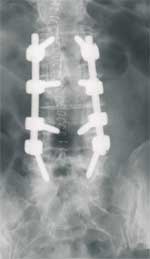

Hier, so soll das nachher ausschauen.

Schöne Grüße

strempel-impl-roe.jpg

strempel-impl-roe.jpg (4.07 KiB) 6921 mal betrachtet

Am Schraubenkopf ist ein beweglicher Metallteil angebracht, durch welchen nach dem Einbringen der Schrauben in die Wirbel zwei Stäbe parallel zur Wirbelsäule eingeführt werden. Es müssen zur Stabilität mindestens vier Schrauben eingesetzt werden. Die Schraubenanzahl ist abhängig von jener der verformten und schmerzhaften Segmente. Dieses Schrauben-Stab-System wirkt wie ein inneres Korsett, erhält aber durch die dynamischen Schraubenköpfe die Elastizität der Wirbelsäule.

Das Einsetzen dieses dynamischen Implantats (Cosmic-System) dauert unter normalen Umständen zirka zwei Stunden. Durch eine besonders schonende Operationsmethode erholt sich der Körper schnell.